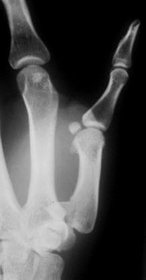

Der Sturz auf den gestreckten Daumen ist meist die

Ursache für diese Problemfraktur. Der Zug der Sehen verursacht

die Dislokation. Die geschlossene Reposition und Gipsfixation kann

die Frakturstellung nicht aufrechterhalten. Die Stabilisierung mit

Kirschnerdrähten, Schrauben oder am einfachsten mit dem Minifixateur

sind die Verfahren der Wahl.